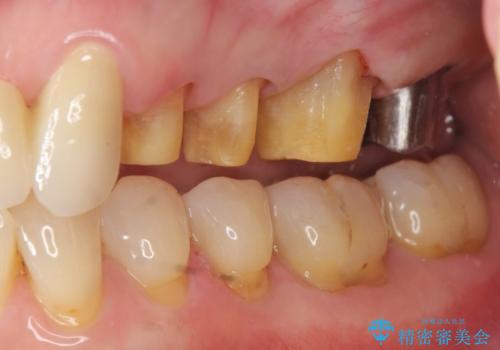

歯ぎしりに抵抗する歯周補綴 インプラント補綴

- 朝起きると歯が痛く歯ぎしり、歯の揺れの改善を求めて来院されました。

噛み合わせ・歯ぎしりにより、歯周病を発症し感染のコントロール、強い咬合力のコントロールをできるような補綴計画をたてます。

分岐部病変を併発していた歯は、抜歯としインプラントによる咬合機能の回復。残すことのできる歯は歯周治療後連結補綴を行い歯ぎしりに対抗します。

夜間のナイトガード装着は必須です。